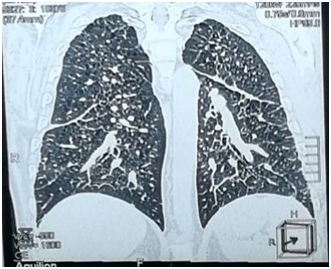

The patient's labs level was within normal except for CRP was elevated. By three separated measurement (one hour between each), water deprivation test revealed increased serum osmolality, increased serum Na+ and decreased urine osmolality. Hormonal Laboratory tests showed decreased FT4 and Testosterone. Magnet Resonance Imaging of pituitary gland was normal and no abnormality was detected (Figure 1). Chest X-ray showed diffuse interstitial reticular densities in both pulmonary fields (Figure 2). X-ray of pelvis and legs showed lytic lesions.

Figure 3 Chest MSCT showing several diffused interstitial reticular densities in both pulmonary fields with small nodular densities.